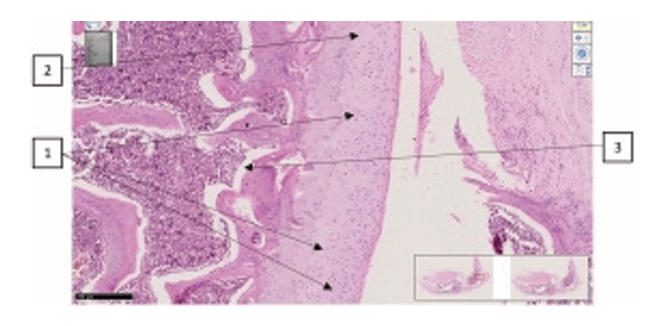

Histological assessment

Various staining methods were employed to assess cartilage integrity, including quantitative evaluation of chondrocytes and nuclear-cytoplasmic ratios. The obtained data were analyzed using the international Mankin scoring system and processed statistically. A comprehensive assessment of joint condition included key markers of chronic osteoarthritis, such as cartilage degeneration, pannus formation, joint space narrowing, synovial membrane alterations, bone tissue changes, and inflammation severity (Figure 3).

Figure 3. Representative histological images of articular cartilage from all experimental groups, stained with hematoxylin and eosin (H&E), periodic acid–Schiff (PAS), and Van Gieson methods. (A) Group I (Intact control) shows intact cartilage with a smooth surface and normal chondrocyte distribution. (B) Group II (Healthy + SCM) demonstrates increased mucopolysaccharide content and mild chondrocyte clustering. (C) Group III (iOA + Postmenopause) exhibits severe degeneration, deep erosions, and cystic resorption. (D) Group IV (iOA + Postmenopause + SCM) displays partial restoration of surface architecture, organized isogenic groups, and preserved extracellular matrix. (E) Group V (iOA + Postmenopause + comparison drug) shows intermediate cartilage damage with reduced PAS-positive staining. (F) Group VI (iOA + SCM) reveals uniform cartilage thickness, large isogenic chondrocyte groups, and a mucopolysaccharide-rich matrix. Arrows indicate changes in the cartilaginous tissue of the rat knee joint: uneven thickness of the surface layer; alteration in hyaline texture with disruption of the row arrangement of chondrocytes in the superficial zone; vacuolar dystrophy detected in the intermediate zone; uneven distribution of isogenic chondrocytes; presence of fibrous foci around isogenic chondrocytes; and reduced homogeneity of the interstitial substance.

Histological analysis was conducted to evaluate the extent of cartilage

degeneration and regenerative changes across all experimental groups.

Group I (Intact control) displayed well-preserved cartilage with a smooth

articular surface, normal zonal architecture, and evenly distributed chondrocytes

at various stages of maturation. The cartilage matrix was dense, with no signs of

erosion or pannus formation. The Mankin score was 1, indicating minimal histological

alterations. Group II (Healthy + SCM) showed a slight increase in chondrocyte

clustering and mucopolysaccharide content, as evidenced by intense matrix staining.

Isogenic groups were aligned along a uniform trajectory within cartilage of consistent

thickness. These findings suggest early anabolic activity without evident

degeneration, with a Mankin score of 2. Group III (iOA + Postmenopause) exhibited

the most severe histopathological changes. The cartilage surface was irregular

with deep erosions and substantial chondrocyte loss. Cystic resorption cavities

filled with adipose tissue were observed, and the bone trabeculae appeared thin

and fragmented. Osteoclast activity was apparent, indicating advanced joint

degeneration. The Mankin score was 12. Group IV (iOA + Postmenopause + SCM)

demonstrated marked improvement compared to Group III. The cartilage surface was

more regular, with evidence of chondrocyte proliferation and moderate vacuolar

dystrophy. Isogenic clusters were organized, and the extracellular matrix was

moderately preserved. The Mankin score was 4. Group V (iOA + Postmenopause +

comparison drug): Showed intermediate cartilage damage. While the articular

surface appeared smooth, PAS staining revealed a reduction in Schiff-positive

matrix components, indicating partial degradation. Chondrocyte density was lower

than in SCM-treated groups. Mankin score = 7. Group VI (iOA + SCM): Showed clear

signs of regeneration. Cartilage layers were uniform in thickness, and large

isogenic groups of chondrocytes were observed. The matrix was rich in

mucopolysaccharides, suggesting enhanced biosynthetic activity. Mankin score = 6.

These histological findings confirm that SCM treatment supports chondrocyte

activity and matrix repair in osteoarthritic cartilage, with particularly favorable

outcomes in postmenopausal animals receiving SCM compared to untreated controls.